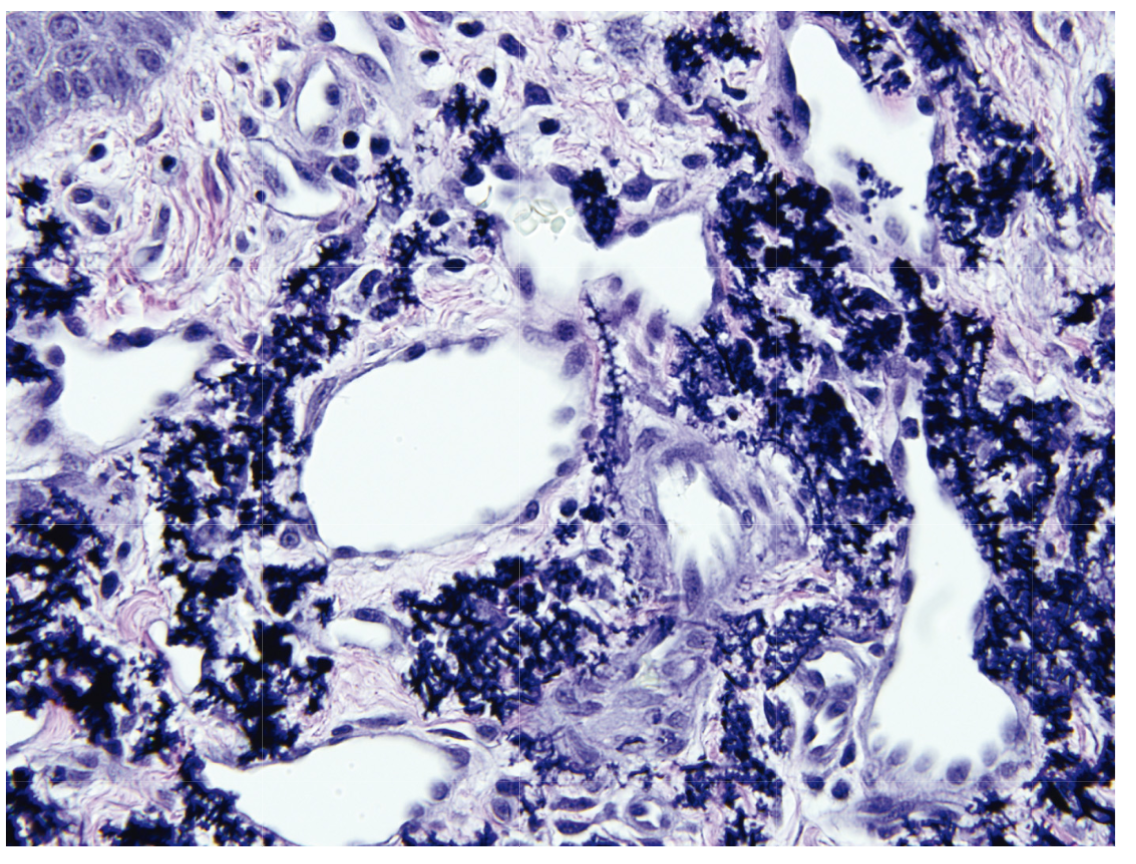

Mastocytoma

TMEP is the same but limited to a superficial perivascular infiltrate

Leder stain - red

CD117 (C-Kit)) - brown

Trptase - brown